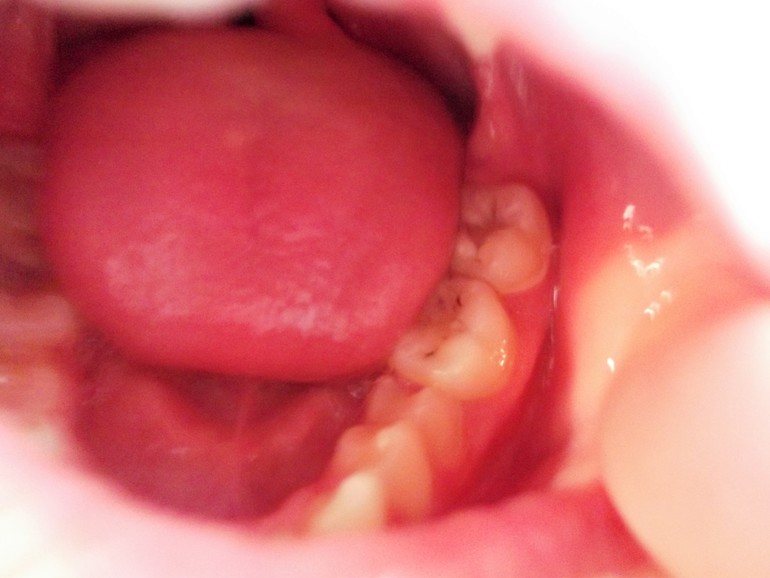

У ребёнка 11 лет.Сидим на обезболивающих.Может есть здесь специалист/ортодонт?

Что сделать на минимальных началах чтобы зуб встал на место?

На фото она нижнюю челюсть вперед выдвинула? Как у нее зубки смыкаются? Катя, напишите на форум, я серьезно. Там вам лучше помогут, чем здесь. Здесь нет ортодонтов. Ну или где-то в сообществе стоматология видела пост от девочки. Она ортодонт.

Болит где именно? В области пятерки? Или где зуб мудрости? Вообще по этому снимку сложно что-то понять, надо панорамный. Ну и ортодонт, да.

нет не зуб мудрости. тот что наклонён и давит на коренной.Болит вся челюсть с этой стороны.

Это пятый зуб? Просто качество снимка совсем не очень... У вас раннего удаления там не было? Молочные зубы не удаляли?

Могу порекомендовать вам написать на стоматофорум. Приложите снимок и спросите совета. Не удаляйте ни в коем случае! Хоть это и кажется проще. Мне кажется, можно даже просто конструкцию сделать на два зуба и переместить быстро.

внешне он почти вылез, а на снимке видно что сильно давит.

Катя, это серьезная проблема с прикусом. Ею надо заниматься. Это ЗУБ, орган, он должен выполнять свою функцию. Вы можете удалить его, но тогда наклонятся соседние и она их быстро потеряет. Зубы сместятся. Это не просто так - раз и все...

Я не специалист, просто сейчас прикусом занимаюсь. А что даст подпиливание? Зуб лезет под наклоном. Такое ощущение, что пятерка молочная пятерка удалена слишком рано и постоянному просто нет места. Что-то делать придется в любом случае... Удалить - это значит нанести сильный урон прикусу(.

Катя, еще напишу. Не претендую на истину, но могу предположить, что боли могут еще связаны с попаданием микробов под это зуб, который наклонен. Там может быть карман. Десна вокруг не воспаленная? Такое состояние называется перикоронит. Чаще всего бывает при прорезывании восьмерок, но с другими зубами тоже бывает, если они неправильно лезут.